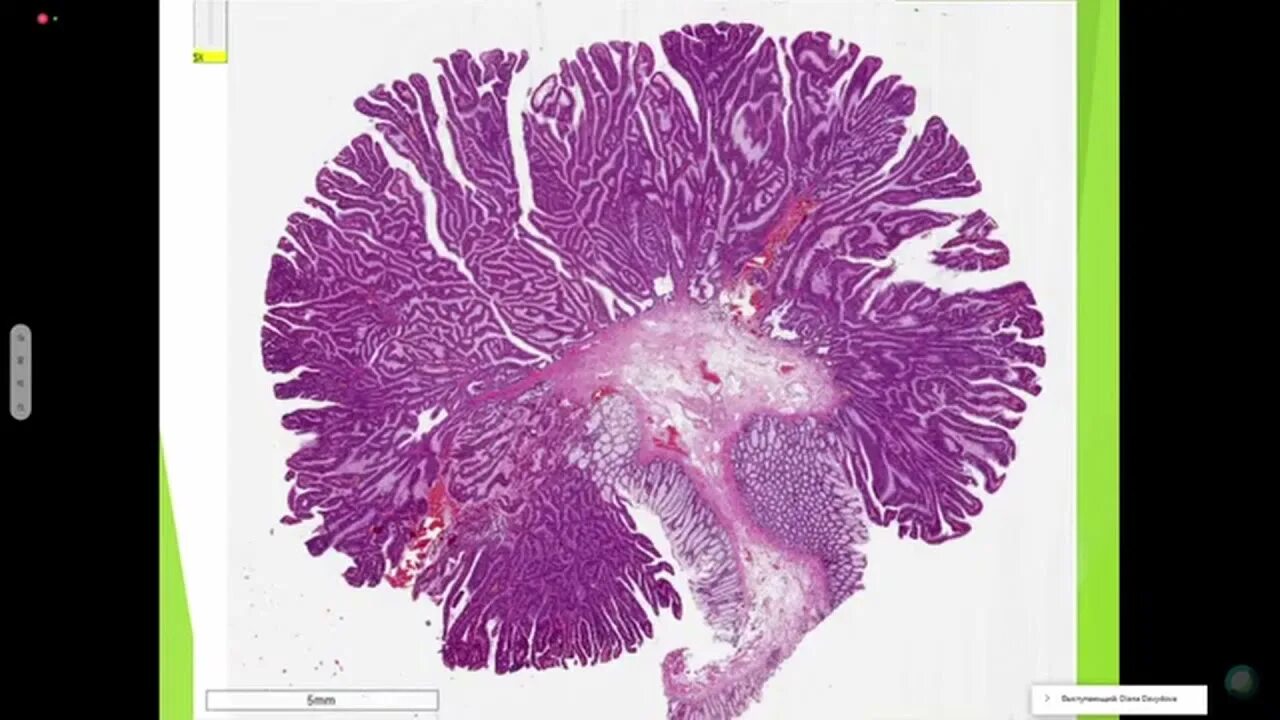

Полипы толстой кишки гистология